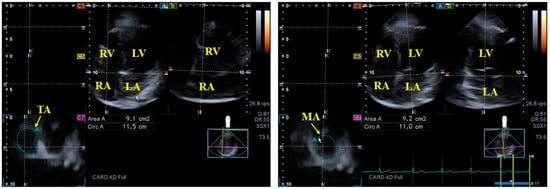

- Nemes, A.; Földeák, D.; Kormányos, Á.; Domsik, P.; Kalapos, A.; Borbényi, Z.; Forster, T. Cardiac Amyloidosis Associated with Enlargement and Functional Impairment of the Mitral Annulus: Insights from the Three-Dimensional Speckle Tracking Echocardiographic MAGYAR-Path Study. J. Heart Valve Dis. 2017, 26, 304–308. [Google Scholar] [PubMed]

- Nemes, A.; Rácz, G.; Kormányos, Á.; Földeák, D.; Borbényi, Z. The tricuspid annulus in amyloidosis with cardiac involvement: Detailed analysis from the three-dimensional speckle tracking echocardiographic MAGYAR-Path Study. Int. J. Cardiol. Heart Vasc. 2022, 40, 101026. [Google Scholar] [CrossRef]